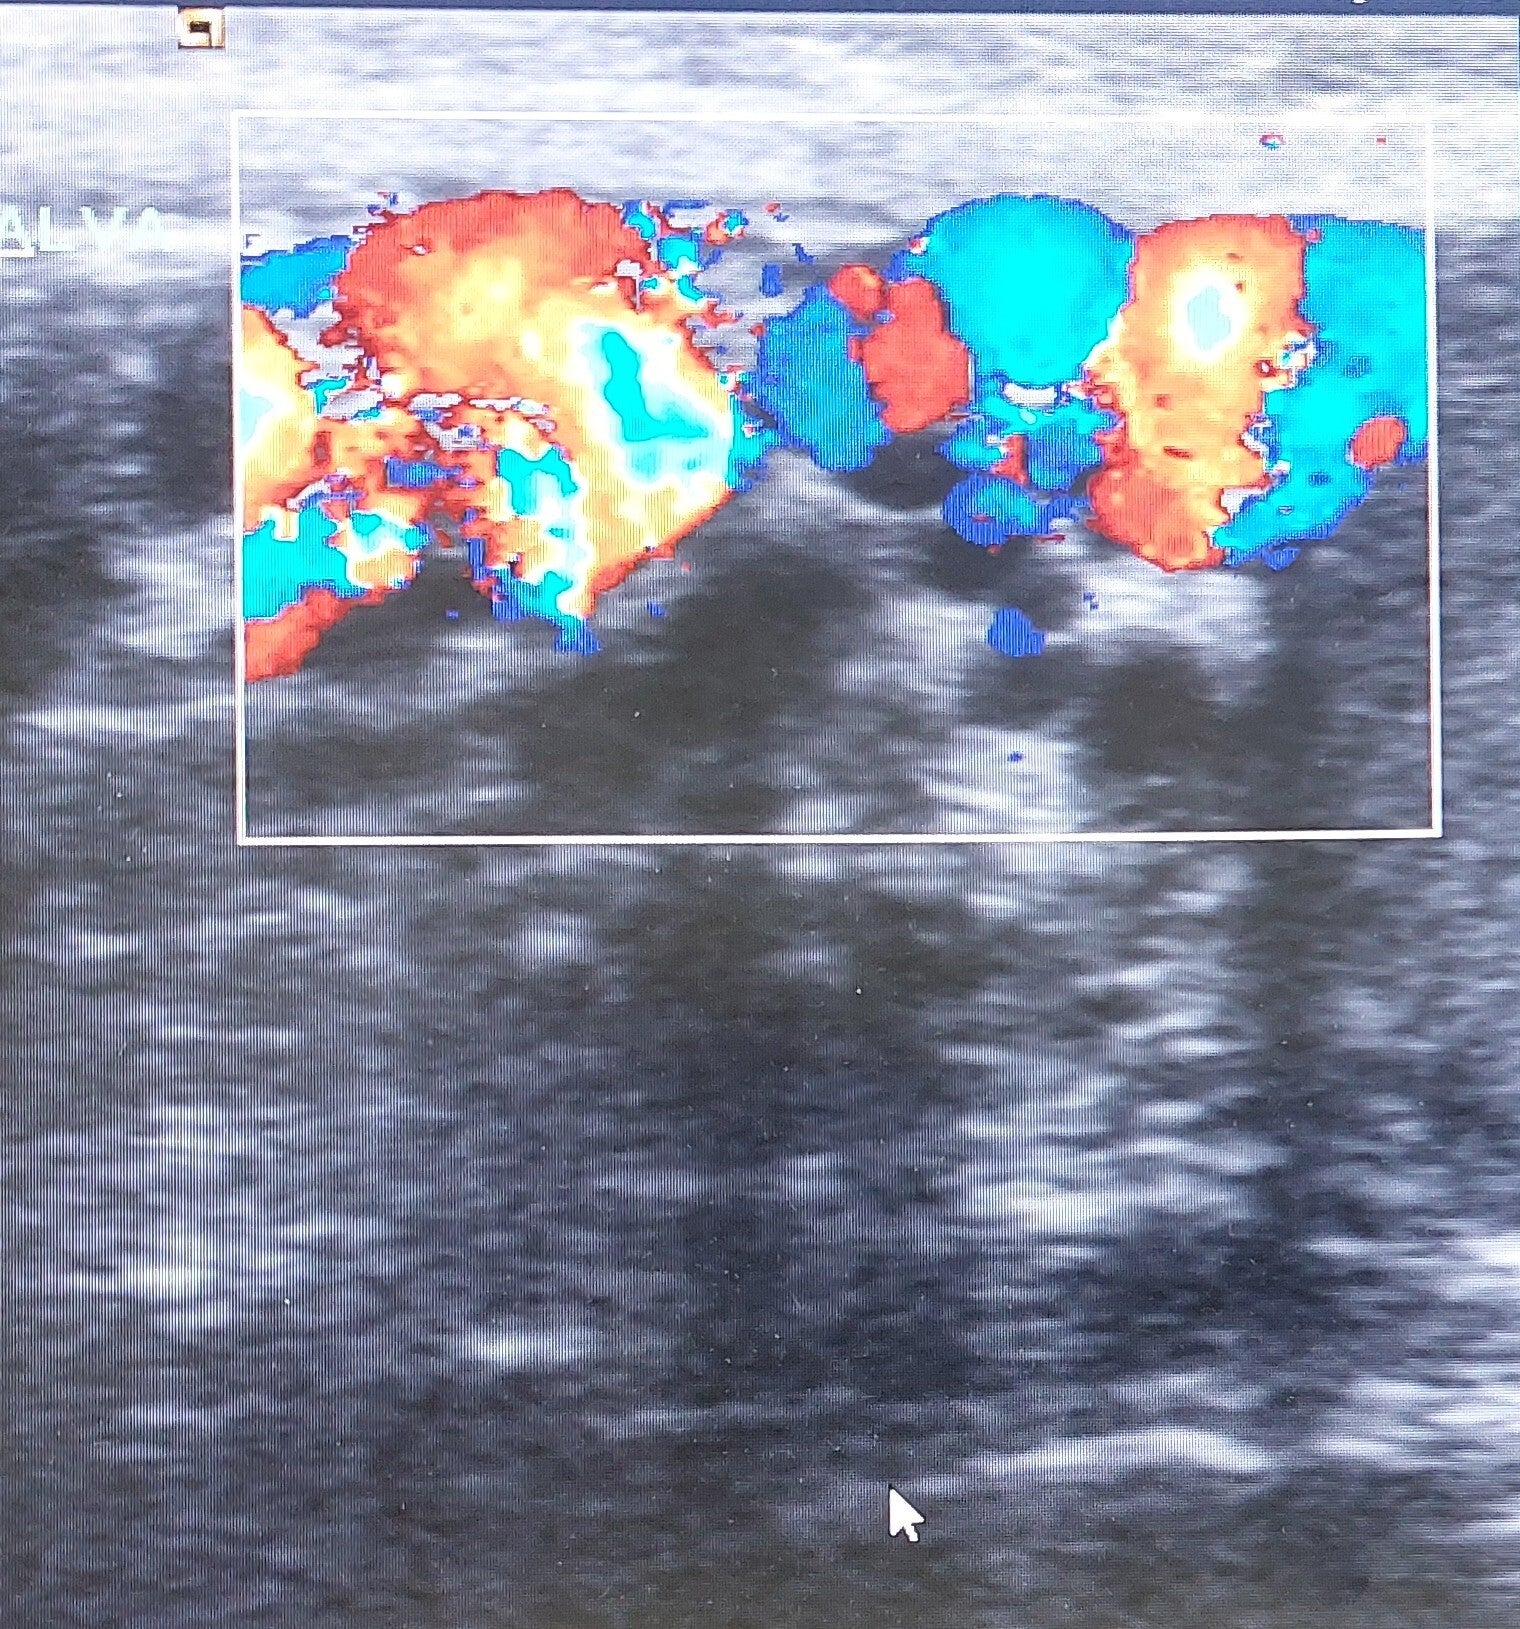

2. Ecocolor Doppler scrotale: È l’esame diagnostico di scelta, che conferma la presenza di vene dilatate e valuta il flusso venoso.